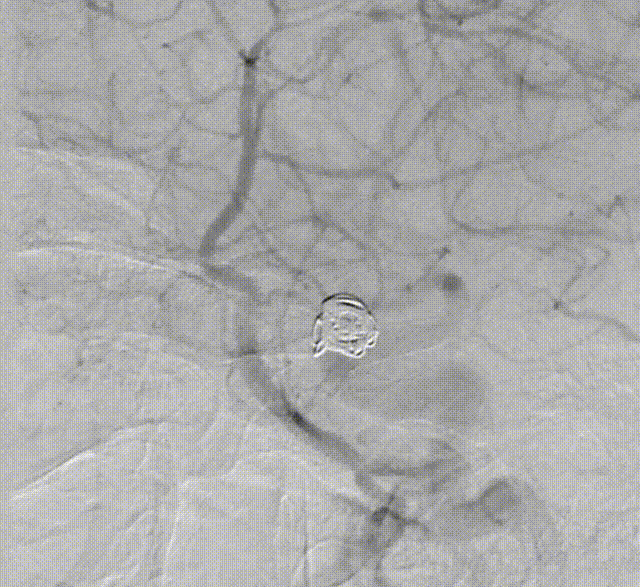

支架导管及弹簧圈微导管先后超选到位,其中弹簧圈微导管超选入远端眼动脉段动脉瘤内备用,根据测量结果,选用YonFlow®血流导向密网支架 4.5mm/30mm、弹簧圈9mm/40cm,先部分推出弹簧圈在动脉瘤内提供保护。再释放密网支架。

1、该病例为串联颈内动脉动脉瘤,符合密网支架应用指征。动脉瘤均位于虹吸段弯曲血管处,跨弯曲的远近段定位不理想时,需要重新回收再释放,对密网支架的操作性能(精准定位、打开贴壁等)有着较高的要求。

2、本例术中应用100%可回收的YonFlow®血流导向密网支架,支架网丝远端头端具有“球头设计”,输送顺滑,可避免管壁损伤,多次回收再释放,帮助术者实现精准定位;其钴铬合金材质网丝可以提供适宜的径向支撑力,又有较好的顺应贴壁表现;创新设计的可控解脱释放方式,可解决目前传统血流导向密网支架临床应用中面临的许多困难,在支架定位、打开贴壁、精准落点、安全性方面带来很大的提升。

3、需要注意的是,在前推解脱杆解脱支架时,突然的张力释放会使支架推送杆少许前窜。因此,在支架定位满意准备释放前,需适当回撤支架推送杆,完全释放张力后,再前推解脱杆,完成支架解脱。